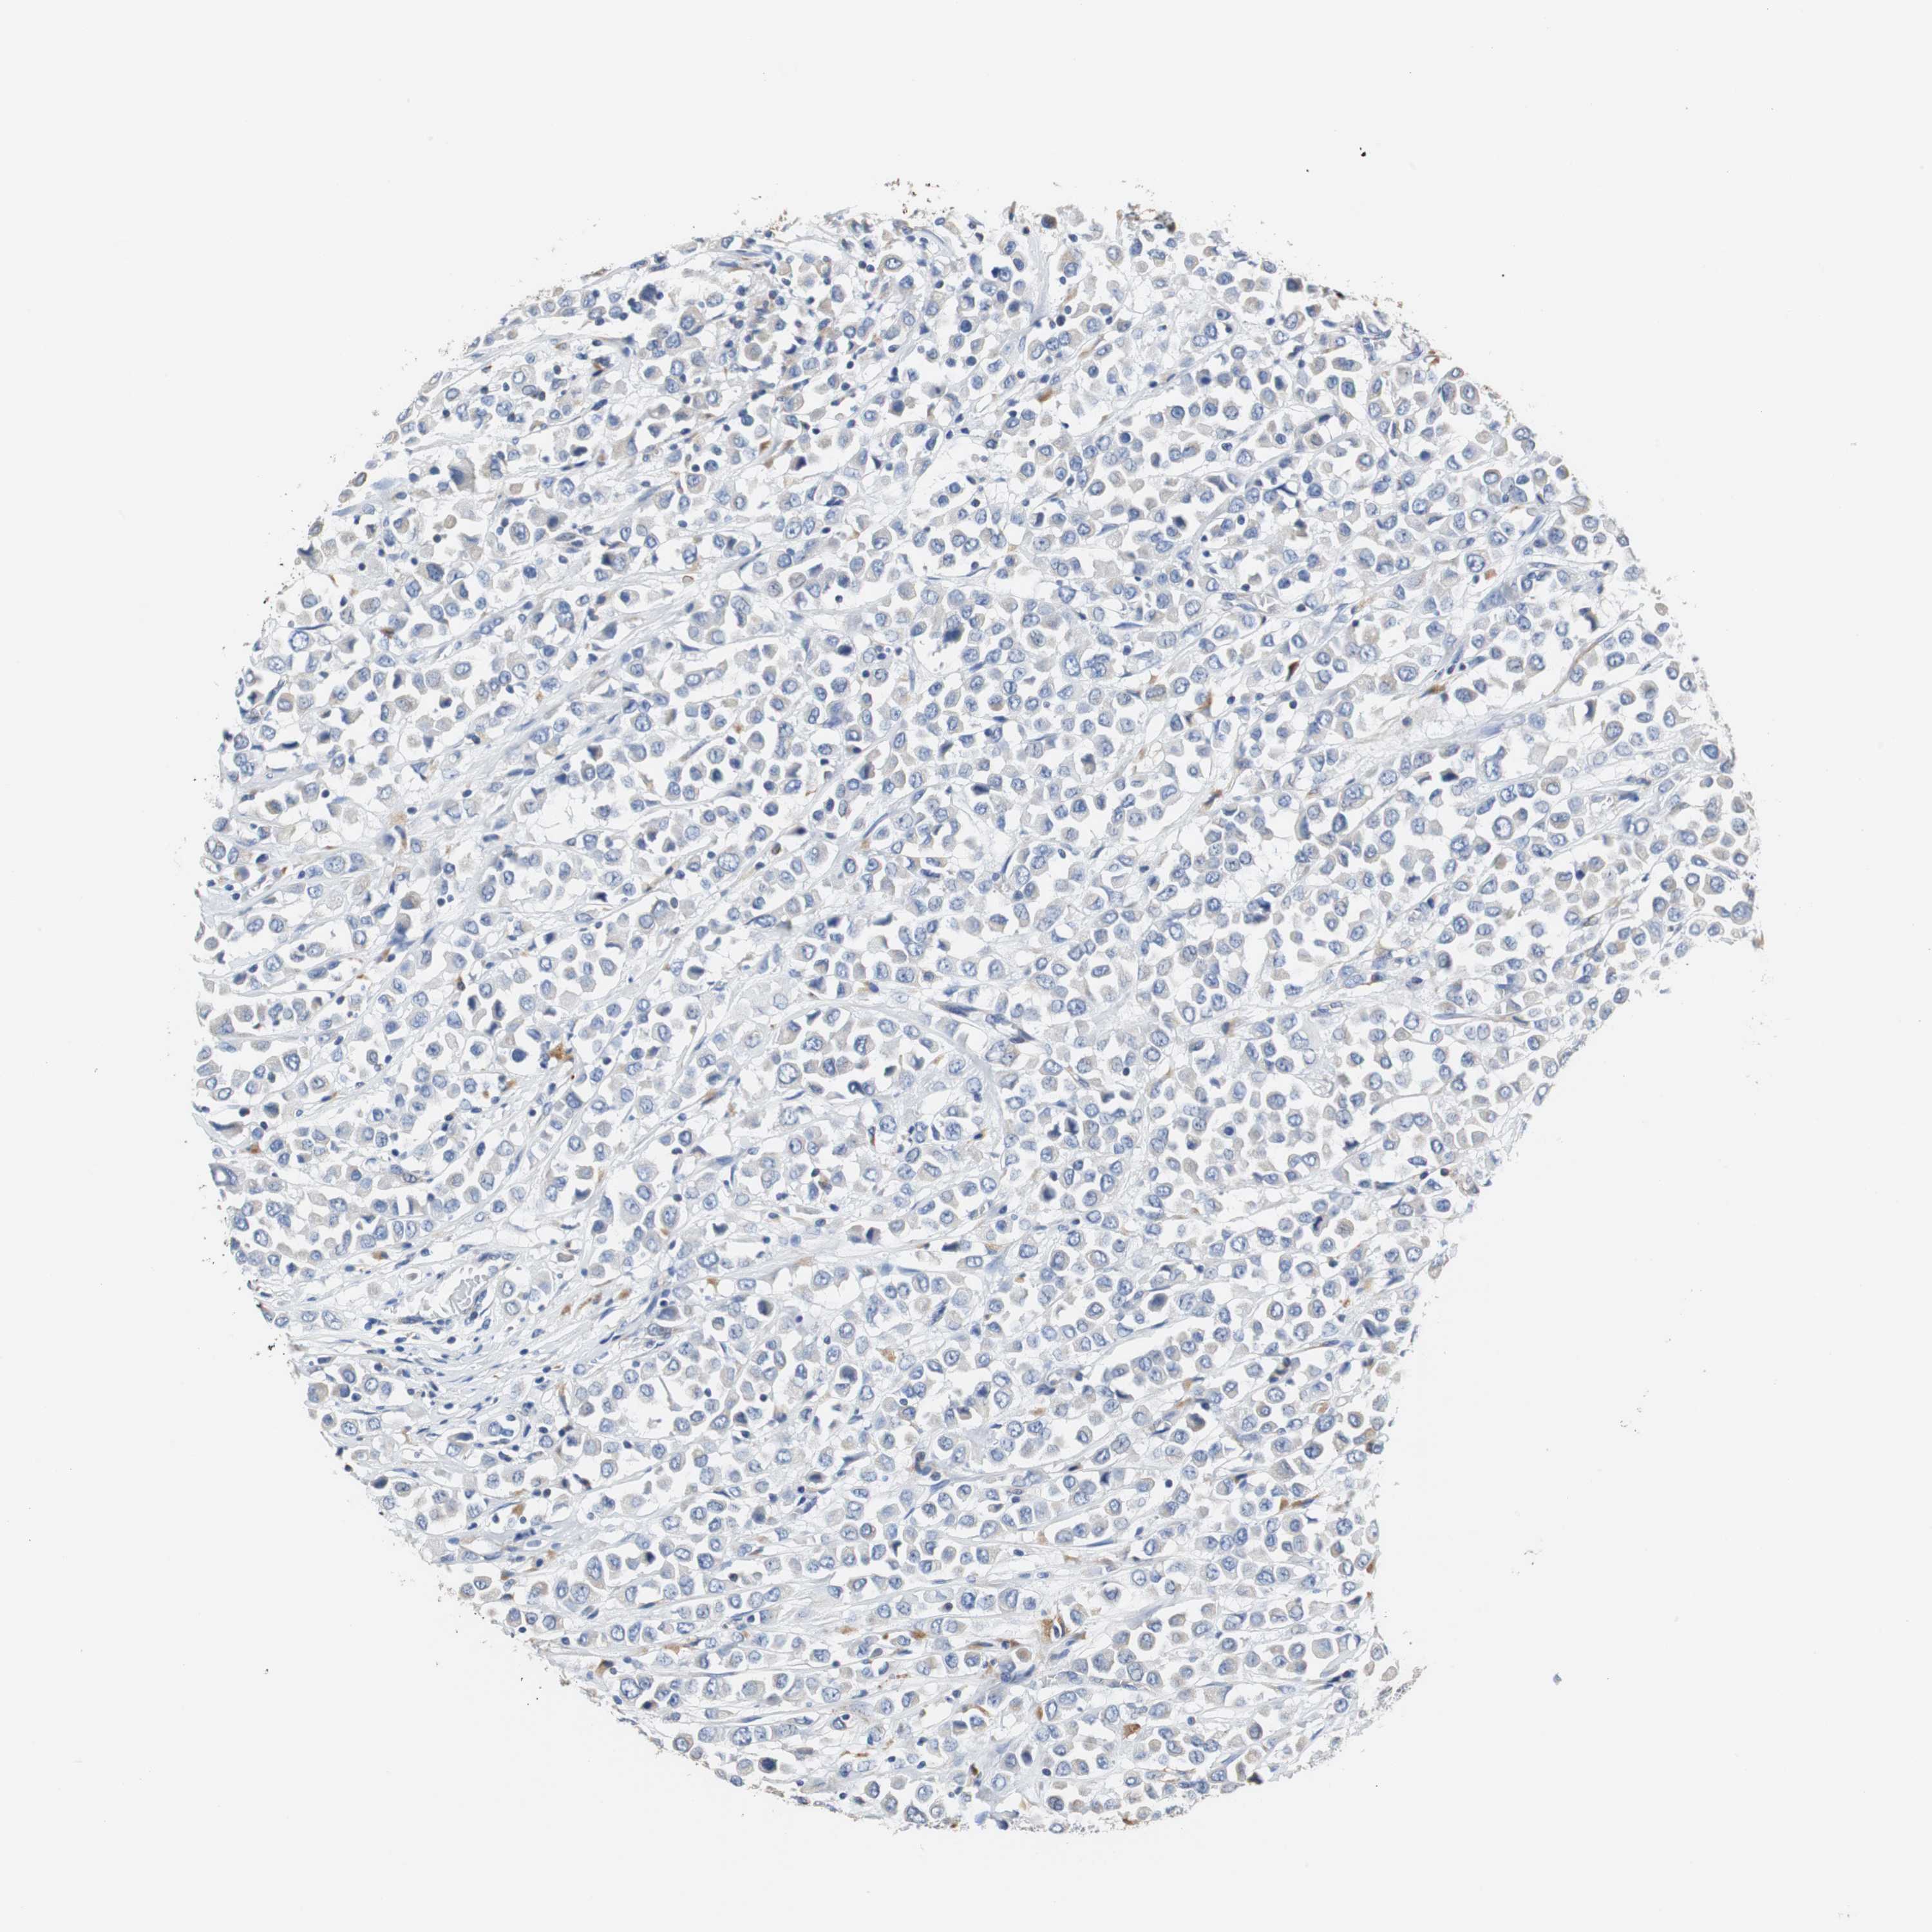

CANCER BREAST CANCER Show tissue menu

BRCA TCGA BRCA VALIDATION PROTEIN EXPRESSION